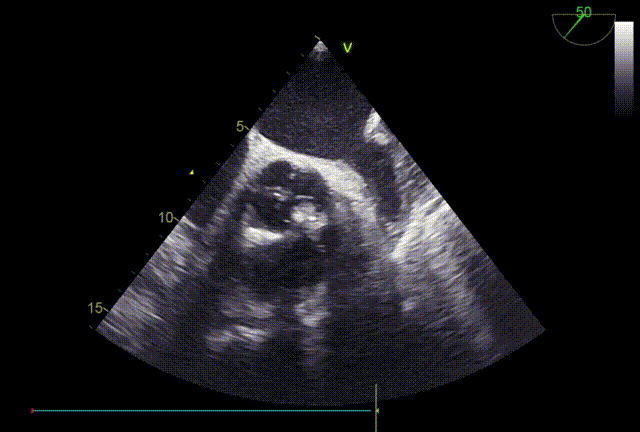

TTE入院

TTE